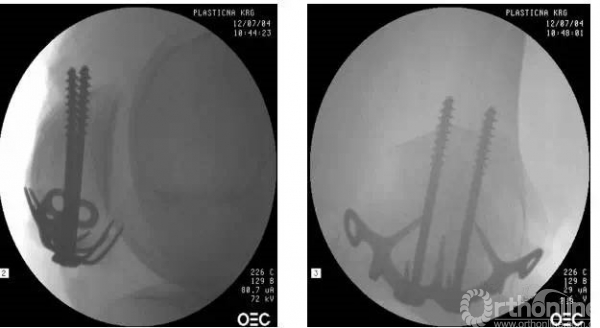

用巾钳加持复位,透视下见复位满意

透视见导针位置满意